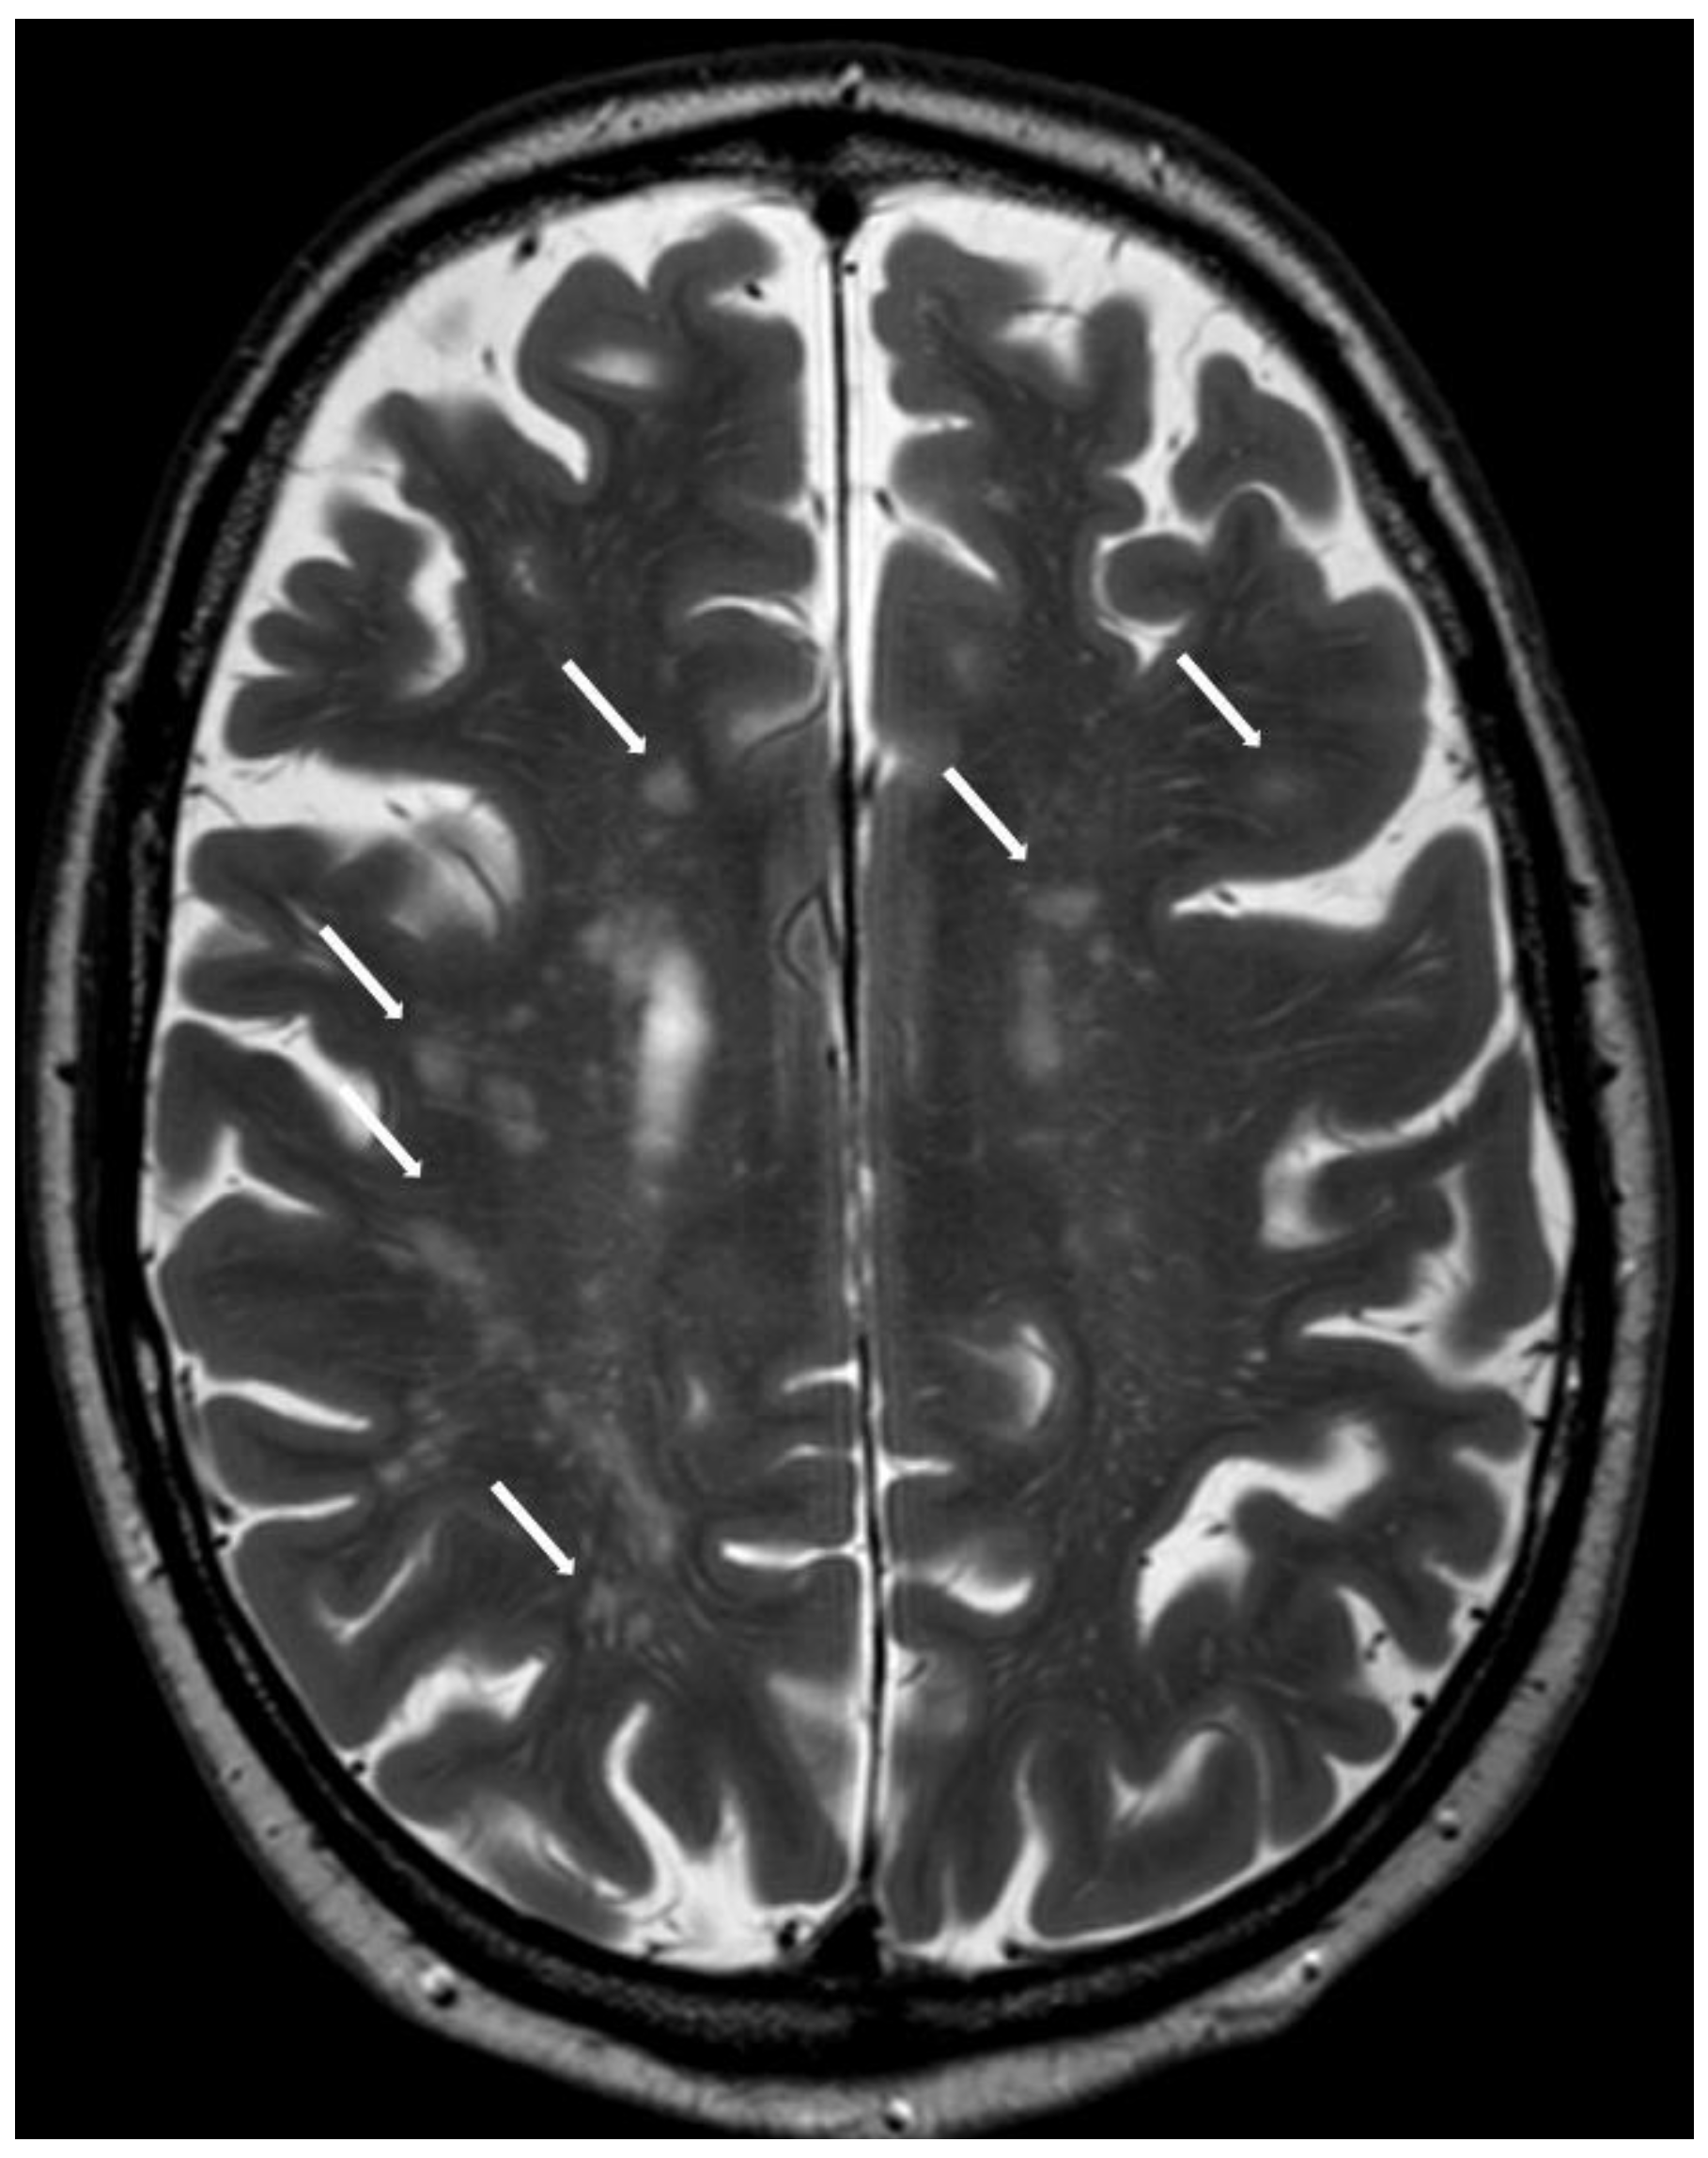

5.2.1. Enlarged Perivascular Spaces

5.2.2. Subcortical White Matter Lesions

6.5. Posterior White Matter Changes